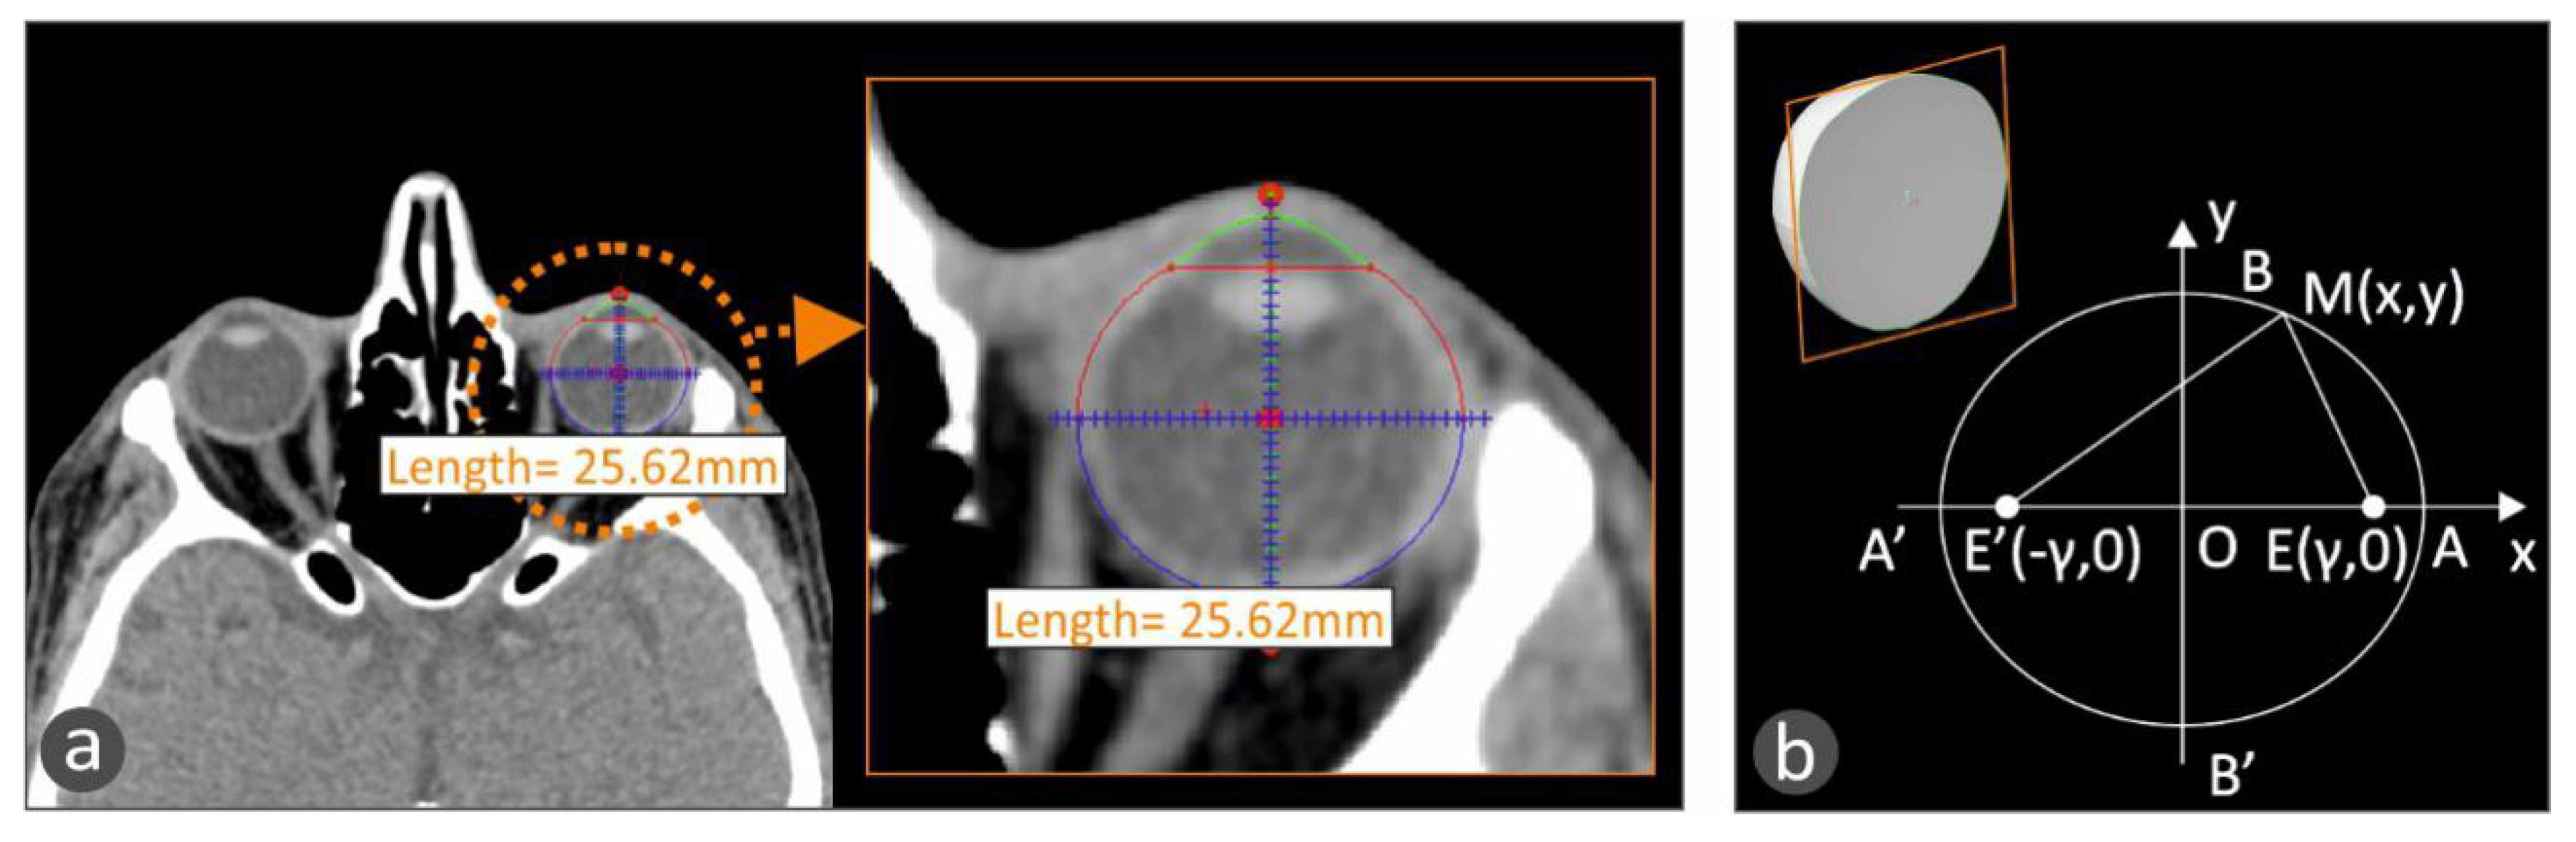

For the development of the tailor-made human eye implant, first, the patient’s eye geometry should be acquired with a medical imaging procedure. Computed Tomography (CT) was chosen, and the patient’s head was obtained primarily with this procedure in the form of medical images for each section taken during the process. The distance between the sections was chosen to be 1 mm. Top-down and front-to-back incisions were taken, and, consequently, there are images that do not contain the eye. With a software tool developed in Matlab Student (Mathworks, MA, USA), every tomography is checked manually, and if there is a part of the eye, the section is further processed. In the CT images that include the eye, the area that includes the eye was isolated. Then, pattern recognition algorithms were employed to isolate the perimeter of the eye in each CT image, which is in grayscale, and the circumference of the eye is selected and stored. In order to more accurately fit the geometry of the eye (Figure 2a), the assumption that each section is an ellipse, as human anatomy dictates [16], was made. An ellipse with focal points E’ (−γ, 0) and E(γ, 0), as shown in Figure 2b, is defined by the following equations:

Figure 2.

(a) Fitting an ellipse in the human eye circumference to more accurately capture the eye geometry in a CT scan image with the developed methodology. (b) The ellipse geometry that the human eye follows, according to human anatomy [16].